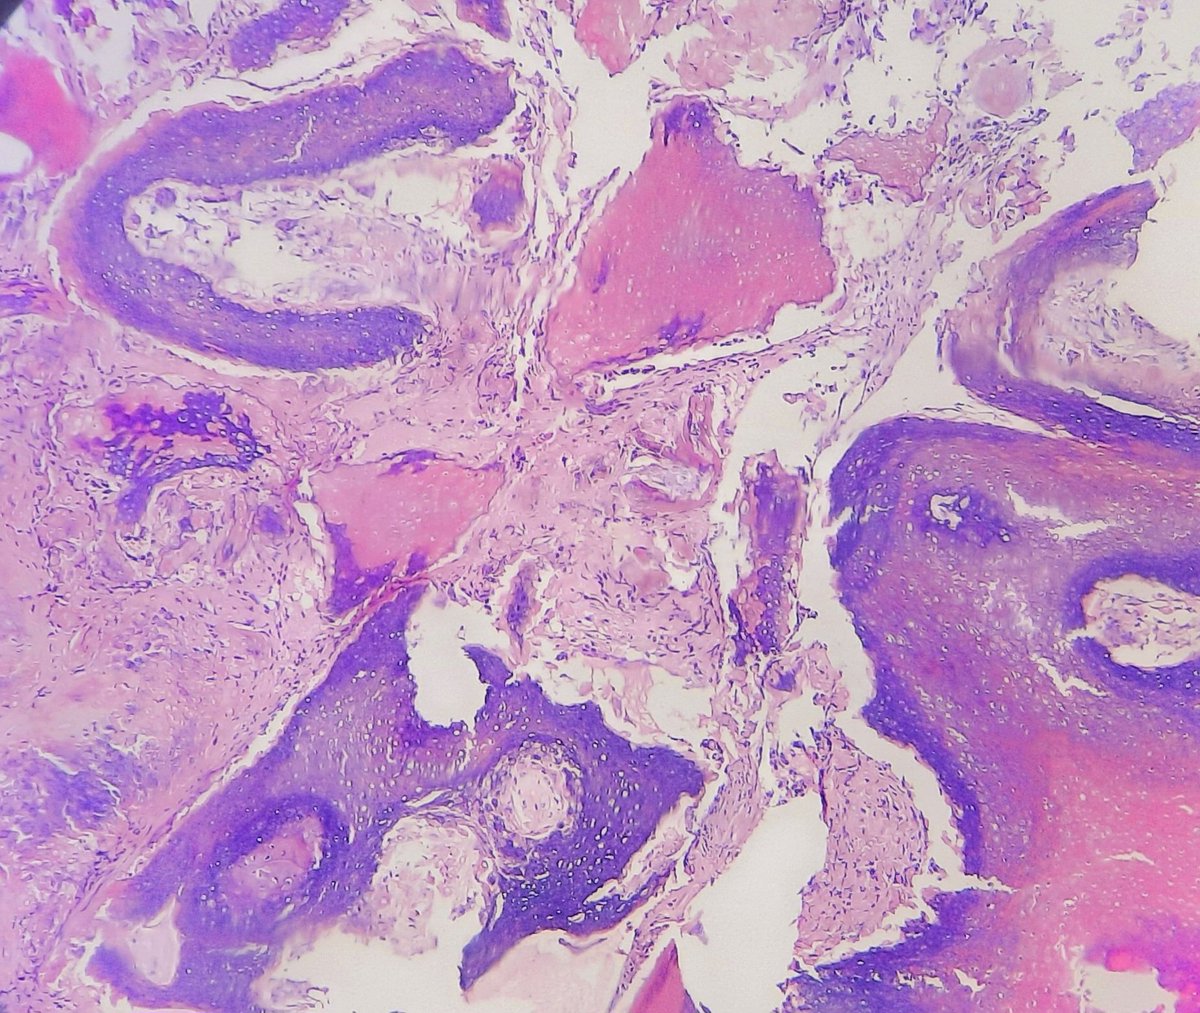

Bladder mass , different biopsies in the background of bilharzial cystitis #pathology #GUpath #twitterpath

LFpath's tweet image. Bladder mass , different biopsies in the background of bilharzial cystitis #pathology #GUpath #twitterpath